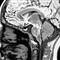

• 脑研究新突破 新型微芯片实时模拟大脑信息处理脑研究新突破 新型微芯片实时模拟大脑信息处理 瑞士科学家最新研制一款微芯片,具备大脑信息处理能力   目前,科学家最新研制一款微芯片,能够实时模拟大脑的信息处理。来自苏黎世大学和瑞士联邦理工学院的神经信息学研究人员证实了复杂识别能力如何结合电子系统,…